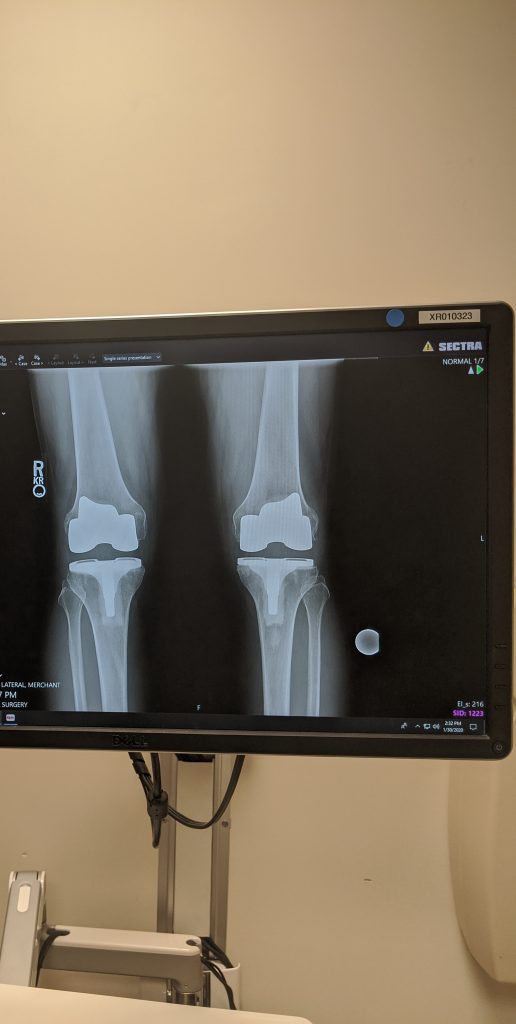

My story beings some 10 years ago when I first started to notice pain in both knees at the same time. The right was worse than that left, but as the years went by the cartilage in both knees slowly dwindled to nothing and I was bone on bone. Leaving me in extreme pain every time I would do anything regarding my knees like, walking, stairs or bike, sat & stood up, bending or running. My quality of life was getting worse and I couldn’t walk 4 blocks without stopping to rest.

The surgery took place December 18, 2019, and took about 4 hours. After 2 days PT was in my room getting me on a walker and having me walk up and down the halls. After 4 days I was trying stairs and longer walks. I stayed in the hospital for 6 days and made it home for Christmas Eve.

Thanks to Dr. Haas and his patented microscopic procedures, I no longer have any knee joint arthritic pain and after just 10 weeks, I am back to work and navigating stairs, driving, sitting & standing with no pain and no complications. I am still in PT and muscles are still recovering and there is some tenderness, but that will go away with time and I can bend my knees more than I could pre-op.